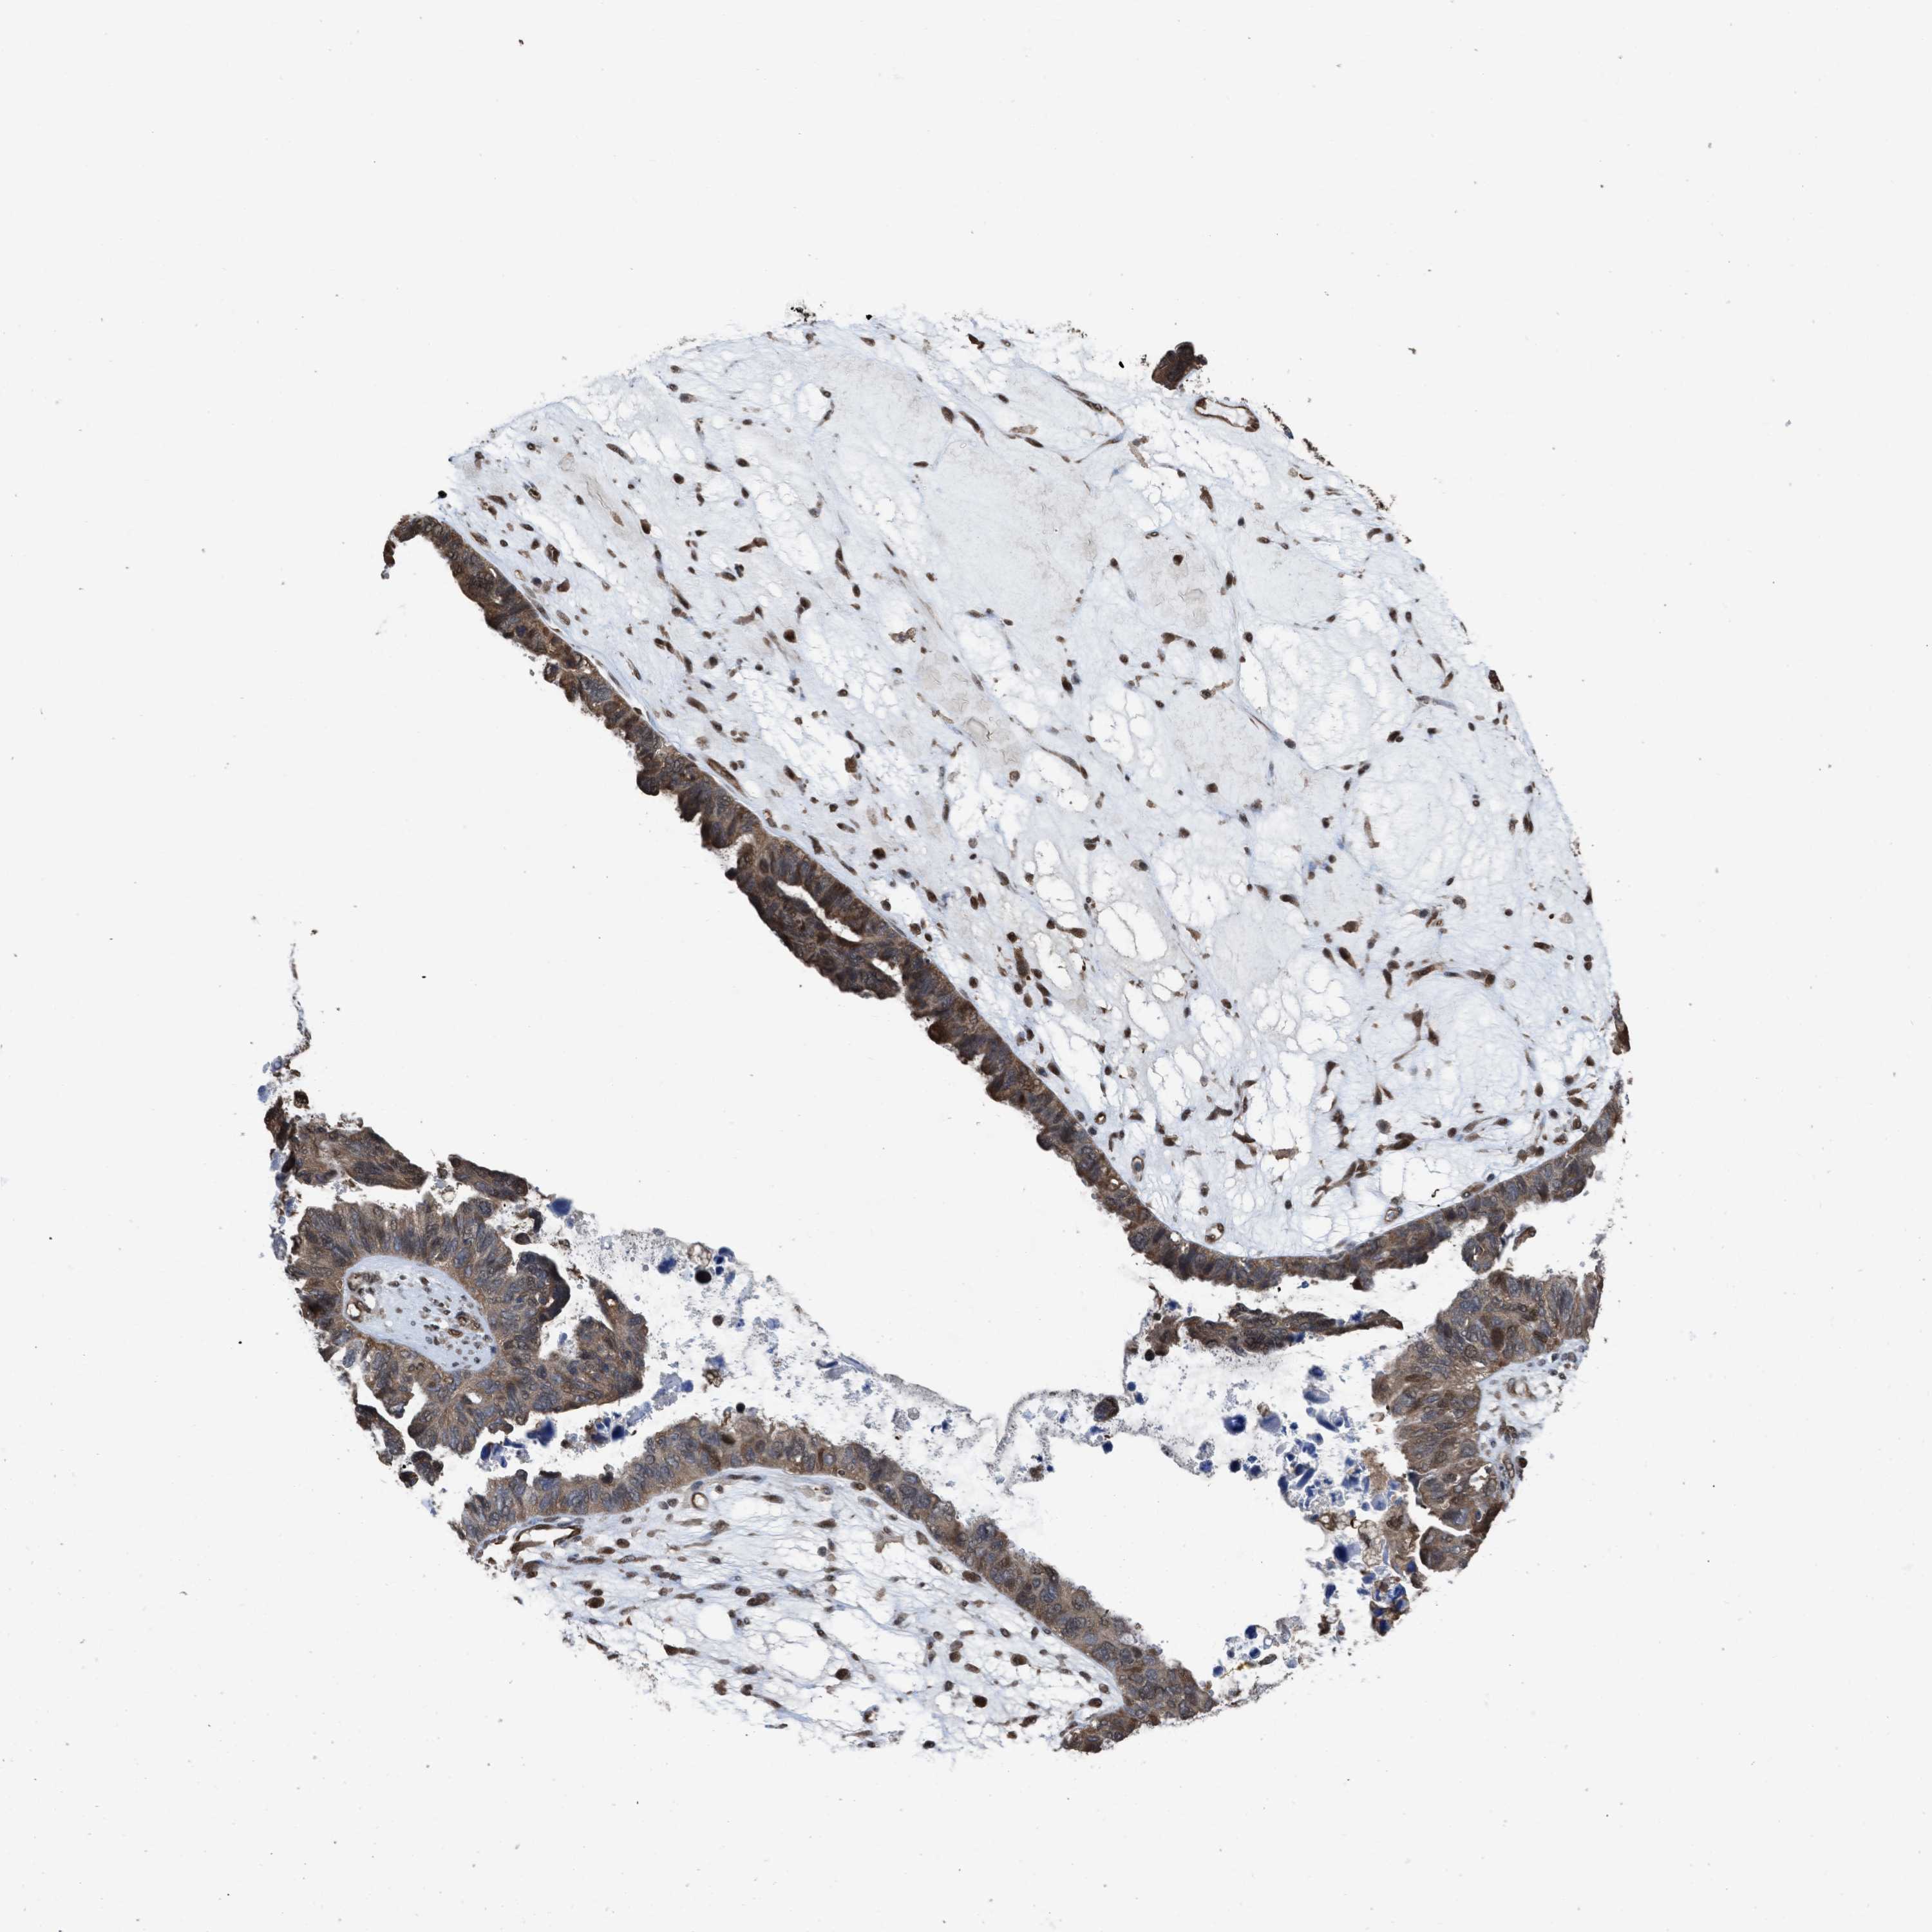

OVARIAN CANCER - Protein expressioni

A mouse-over function shows sample information and annotation data. Click on an image to view it in a full screen mode. Samples can be filtered based on level of antibody staining by selecting one or several of the following categories: high, medium, low and not detected. The assay and annotation is described here.

Note that samples used for immunohistochemistry by the Human Protein Atlas do not correspond to samples in the TCGA dataset.

Antibody stainingi

Antibody staining in the annotated cell types in the current human tissue is reported as not detected, low, medium, or high, based on conventional immunohistochemistry profiling in selected tissues. This score is based on the combination of the staining intensity and fraction of stained cells.

Each image is clickable and will lead to virtual microscopy that enables deeper exploration of all samples and also displays staining intensity scores, fraction scores and subcellular localization as well as patient and tissue information for each sample.

Antibody HPA026918

Antibody CAB013274

Antibody CAB018389

Cystadenocarcinoma, serous, NOS

Carcinoma, endometroid

Cystadenocarcinoma, mucinous, NOS

Carcinoma, NOS